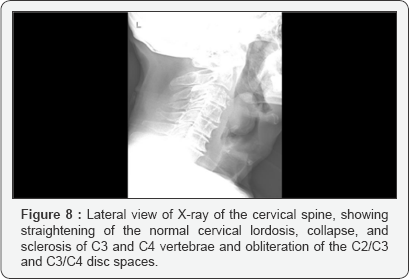

Complications

Pott disease is the most dangerous form of musculoskeletal tuberculosis because it can cause-bone destruction, deformity, paraplegia, resulting from spinal cord compression usually respond well to chemotherapy, sometimes operative decompression is required motor deficit -a nerve is compressed Association impairment scale (ASIA) is useful to document neurological recovery from Pott disease. A designation of ASIA A indicates the most severe neurological compromise, ASIA E the least. At the beginning of treatment, most individuals are characterized as ASIAD. Late-complication can still occur reactivation of TB instability or deformity of the spine (Figures 8 & 9) [13-17].

Lab test: CBC anemia, neutropenia, lymphocitosis ESR- elevated, 72mm/hr (Westergreen method). PCR elevated -microbiology-sputum, BK direct, cultures -HIV screening negative IDR at PPD+ -QuantiFERON test + ImagisticS -X-ray chest showed reticulo-nodular shadows in both apices but worse on the left.-X-ray cervical spine showed: Straightening of the normal cervical lordosis, collapse, and sclerosis of C3 and C4 vertebrae and obliteration of the C2/C3 and C3/C4 disc spaces. Other findings include widening of the prevertebral soft tissue from C1-C5 with resultant narrowing of the adjoining airway (oropharynx and hypopharynx). There was also sclerosis of the pedicles of C3/C4 vertebrae and osteophytic spurring of the antero-superior margin of C4. Lesions of the cervical spine cause neurologic deficit more frequent because the spinal canal in this region is small relative to the diameter of the cervical cord. The mechanism of neurologic symptoms in cervical spine TB include: local inflammation, tuberculous vasculitis and ischemia, subluxation of the vertebrae, abscess on the spinal cord or nerve root, and impingement of the discs. He was admitted in the ICU for rapid respiratory failure caused by paralyzed respiratory muscles intubated and put on mechanical ventilation. Tracheostomy was another must to do procedure plus drainage of the retropharyngeal space. Even of the good coverage with antibiotics -Meropenem plus Vancomycine, plus Isoniazid, Streptomycin, Ethambutol and Ryfampin he developed a severe bronchopneumonia with multirezistant Acinetobacter -and after a long treatment including Colistine sulphat he was clean but very weak. He continue the treatment immobilized and ventilated ,he was proposed for laminectomy but he died on surgery because of extremely late presentation.